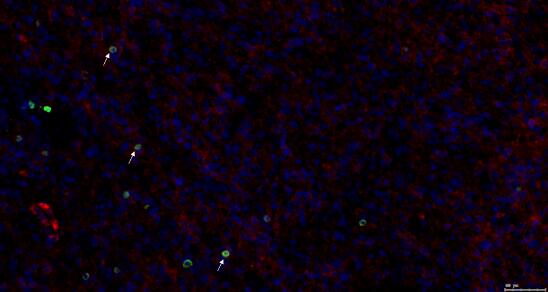

识别特殊细胞及其功能状态——通过共定位标示性 Marker 蛋白

双定位(两个蛋白):

三共定位(三个蛋白):

四共定位: